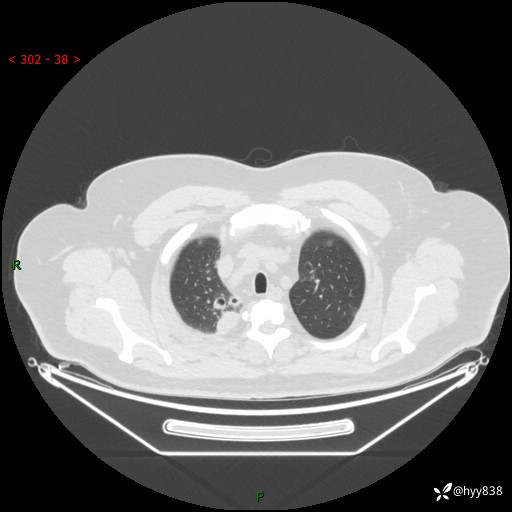

性别:男

年龄:48岁

简要病史:发热来诊(门诊病人)

胸部CT平扫